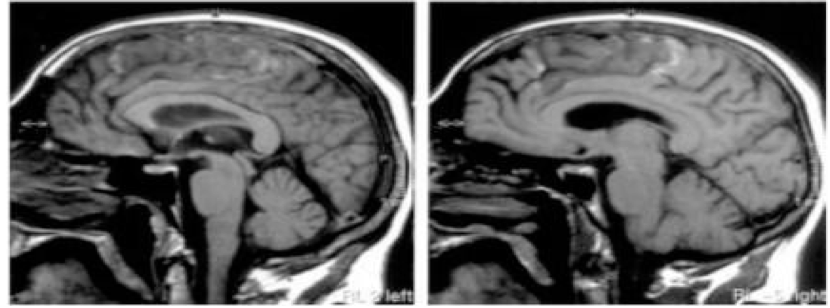

This scientist remove the cerebral hemisphere from the rest of the brainstem of a cat and kept the cat alive

He elicited reflexes by stretching the hind leg of the cat

Before decerebration, he found that when he stretched the cat’s leg, the muscle in the hind leg contracted in a reflex action

After decerebration, when he stretched the hind leg he found that there was a HUGE INCREASE IN THE SIZE OF THE RESPONSE generated by the muscle and there was a lot MORE TONE that remained after the muscle had been stretched

This is similar to the spasticity seen in an arm or leg in someone who has had a stroke

IMPORTANT: if you remove the descending inhibitory control then you will get very BRISK REFLEXES and SPASTICITY in muscles